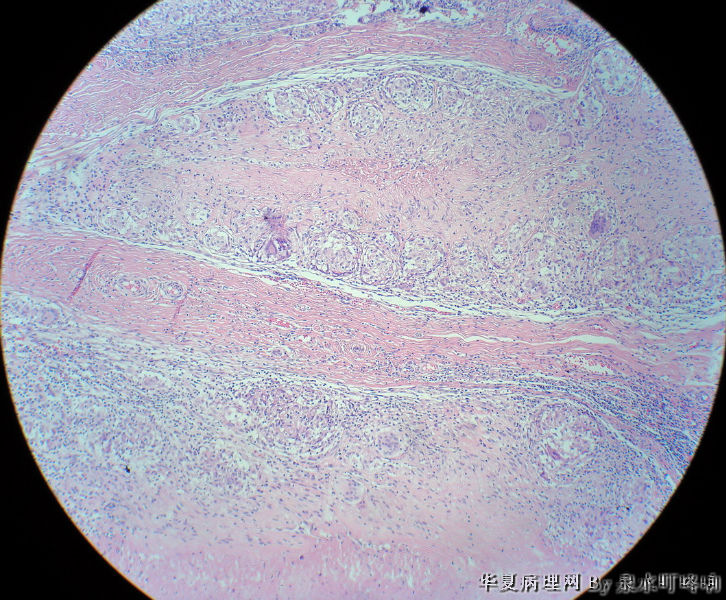

左腋窝肿物

• 左腋窝肿物图2

图2

女,3岁,主因左腋窝肿物半年,术中见为肿大淋巴结,淋巴结内有脓液及坏死组织。

大体:灰红色组织一块,大小约4.6×3.5×2厘米,切面可见两个囊性区域,内容乳白色浓稠液体。

肉芽肿性炎(建议做抗酸染色,除外结核)

是淋巴结吧,淋巴结肉芽肿性炎伴坏死,建议做抗酸染色。

肉芽肿性炎,考虑结核伴钙化。